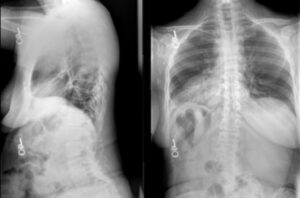

Dr. Robert Eastlack performs L2-pelvis fusion with iFuse TORQ® and iFuse Bedrock Granite® for spinopelvic stabilization and SI joint fusion.

Dr. Jay Turner performs T10-pelvis fixation utilizing 4 iFuse Bedrock Granite® implants to provide multiple points of fixation to the pelvis.